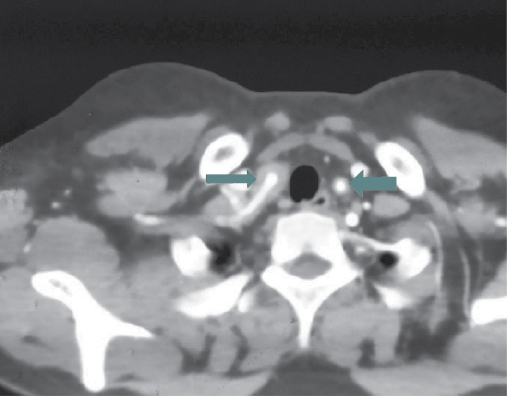

Arterial Doppler of upper limbs showed significant stenosis in the proximal subclavian artery. CT angiogram of brain (Fig. 3) and chest (Fig. 4) showed complete occlusion of right common carotid artery and 50% occlusion of left common carotid, 20% to 30% luminal narrowing of both internal and external carotid artery, occlusion of left and right vertebral artery, both subclavian artery occlusion (30% occlusion), both axillary, brachial, radial, ulnar artery and descending thoracic aorta (20% occlusion). Renal arteries, abdominal aorta, external and internal iliac arteries on both sides were normal.

Figure 4. CT angiogram of chest blood vessels – mural thickening seen in both the subclavian arteries.